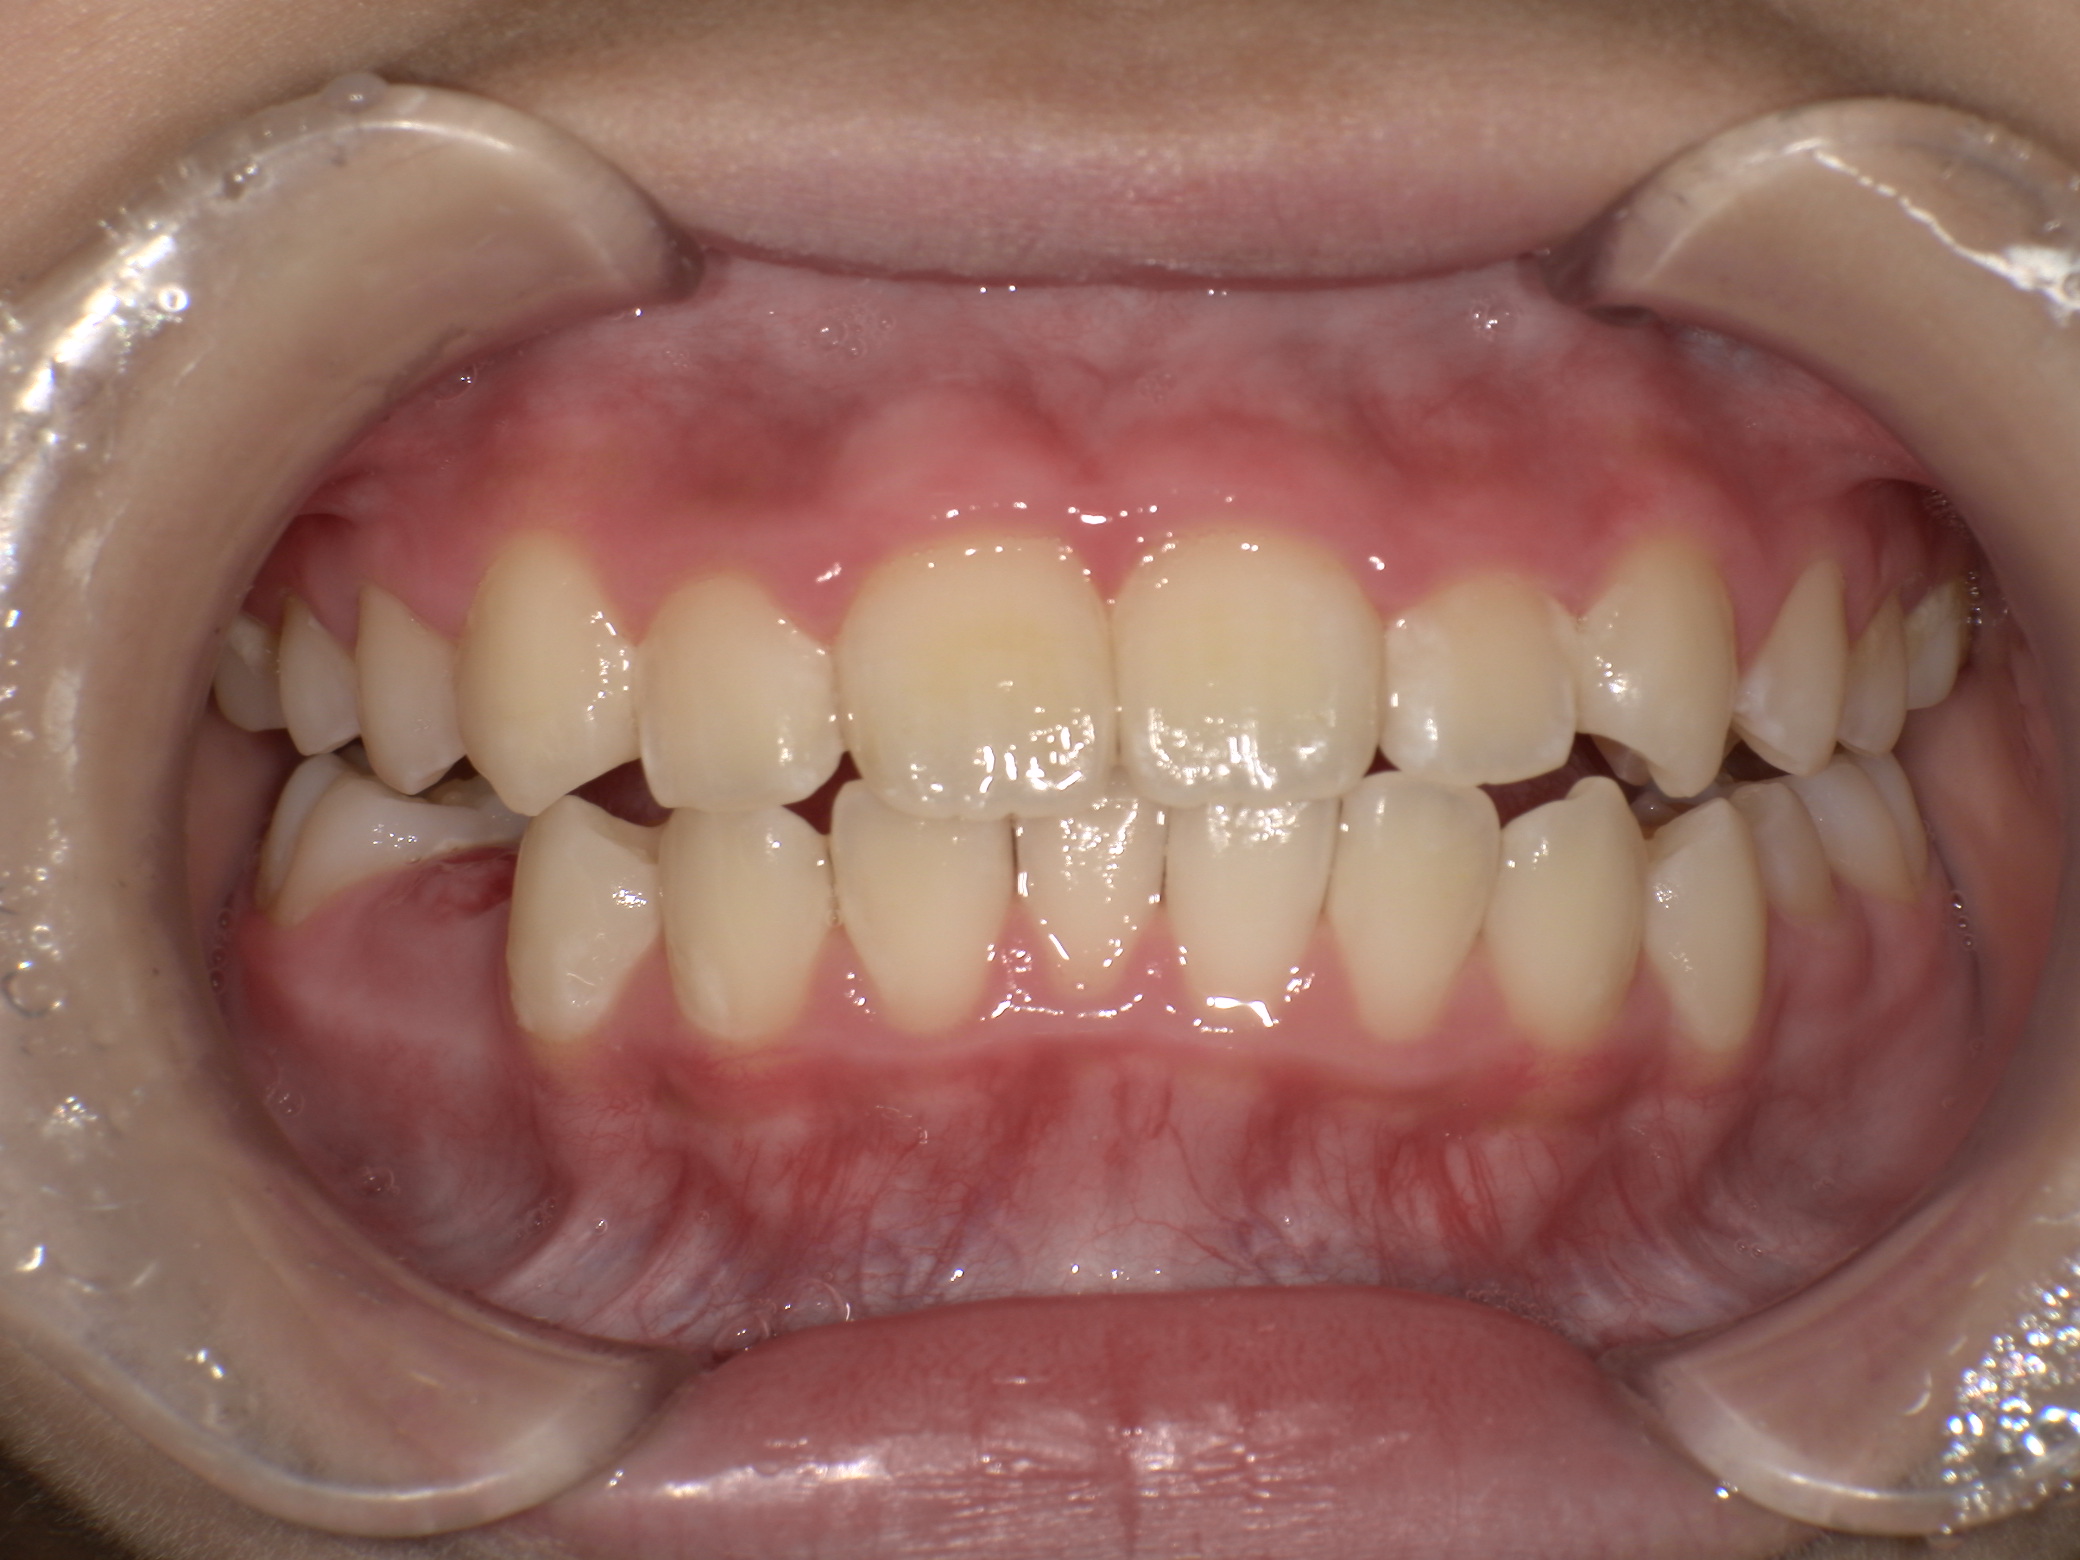

上歯前突+叢生症例 成長期

主訴 | 口元の突出感と歯並びが気になり、将来的な咬合状態を整える目的で来院された患者様です。 |

---|---|

診断結果 | 11歳1か月の女性。骨格的には日本人標準に近く、歯性の上顎前突および叢生が認められました。上下顎ともに歯列のスペース不足があり、永久歯の萌出や歯列の整列に支障をきたす可能性があると診断されました。 |

治療内容 |

|

治療後の経過 | 動的治療終了後は、上下顎の歯列が整い、口元の突出感と叢生が改善されました。審美的・機能的なバランスが取れた状態となり、現在は取り外し式リテーナーを使用し、保定期間に移行しています。 |

治療期間 | 動的治療期間:2年6か月 通院回数:25回 |

治療費用 | 720,000円 |